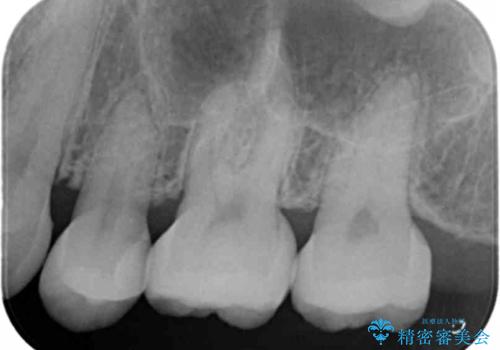

特に大きな虫歯もなかったため、周りの歯を残しつつセラミックインレーでの修復処置をしていきます。

大きな虫歯さえなければ、銀歯のやり替えは詰め物の周りの歯を保存しつつ修復することができます。